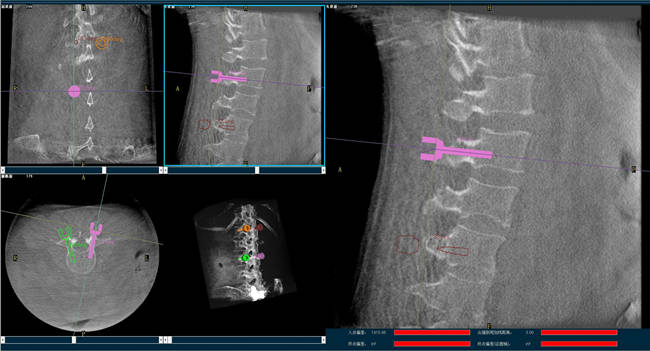

迄今,術(shù)前規(guī)劃已經(jīng)成為骨科手術(shù)的“前哨守衛(wèi)”,目前的脊柱外科手術(shù)機(jī)器人可以通過(guò)人工智能算法做到精準(zhǔn)的脊柱分節(jié)段識(shí)別并模擬重現(xiàn)患者的生理特征與骨骼排列,讓手術(shù)既準(zhǔn)確又安全;尤其在脊柱外科手術(shù)中可以發(fā)揮很大作用,避免產(chǎn)生對(duì)周圍神經(jīng)、椎管內(nèi)脊髓的損害,減少并發(fā)癥的出現(xiàn)。

以椎弓根螺釘置入手術(shù)為例,有時(shí)候?yàn)榱藴?zhǔn)確定位,甚至需要將椎弓根螺釘多次進(jìn)出、反復(fù)選擇,這樣無(wú)疑就增加了脊髓神經(jīng)損傷的風(fēng)險(xiǎn),降低了螺釘把持力。但脊柱外科手術(shù)機(jī)器人可以在術(shù)前規(guī)劃把手術(shù)入路、方向、釘子的深度都做好規(guī)劃,手術(shù)前就在電腦上規(guī)劃好進(jìn)釘?shù)奈恢?,在手術(shù)中利用機(jī)器人系統(tǒng)“(脊柱)分節(jié)段單椎體識(shí)別”、“釘棒一體化”、“術(shù)中全程可視”等特性,做到“一步到位”,因此,比起傳統(tǒng)手術(shù),機(jī)器人手術(shù)更加安全。同時(shí),目前機(jī)器人技術(shù)的透視檢查時(shí)長(zhǎng)、每顆螺釘置入時(shí)長(zhǎng)和住院時(shí)長(zhǎng)均比術(shù)中使用3D-CT導(dǎo)航更短,提升手術(shù)效率。